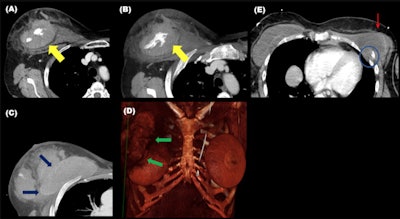

Chest wall injuries tend to align along the axis of the belt. Ribs and sternal fractures are the most common chest wall fractures, but clavicles can also be involved. Sternal fracture is better seen in the sagittal plane and the underlying anterior mediastinal hematoma is better assessed in the axial plane, and fractures of the chondrocostal union are better seen with a soft-tissue window, they stated.

Although rare, breast implant ruptures may occur. These and soft tissue injuries of the chest wall are more frequent when the shoulder harness does not lay over osseous structures.

Fractures of the chest wall are often accompanied by lung contusions and hemopneumothorax. In severe collisions, thoracic aortic rupture through the isthmus or dissection can occur. Other types of intimal injuries are pseudoaneurysms or intimal defects with no aortic contour abnormality.

"Diaphragmatic ruptures are caused by the mispositioning of the lap belt, the sliding of the occupant under the belt during the impact, and the high increase in the intraabdominal pressure," the authors wrote. "They are better assessed in the coronal plane, and fractures or angulation of the ribs and subcutaneous emphysema can be clues."